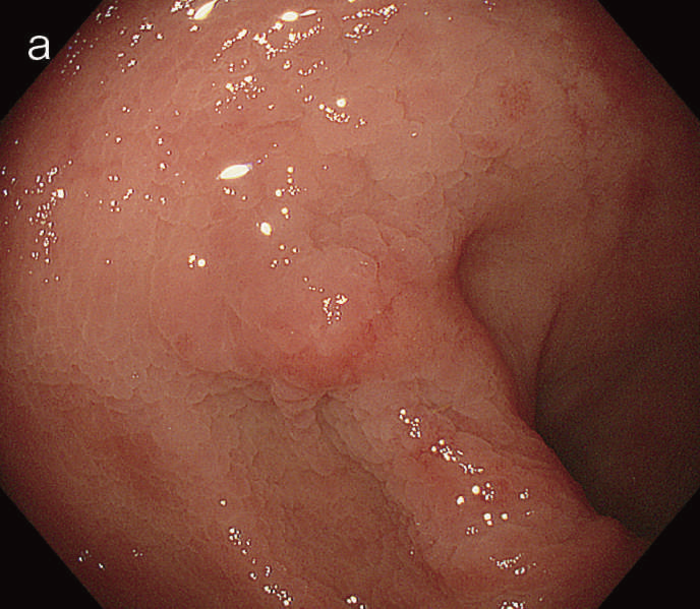

図5 UC関連粘膜下層浸潤癌の内視鏡所見

- 白色光像:直腸(直腸S状部)の発赤調変化。背景粘膜は寛解期にあった。

- 色素内視鏡像:病変辺縁が明瞭となるが,病変肛門側で不明瞭であった。

- NBI拡大像:口径不同,不均一な微小血管と不整な表面構造所見を認めた。

- pit pattern像:小型の類円形,管状pitを認めた。